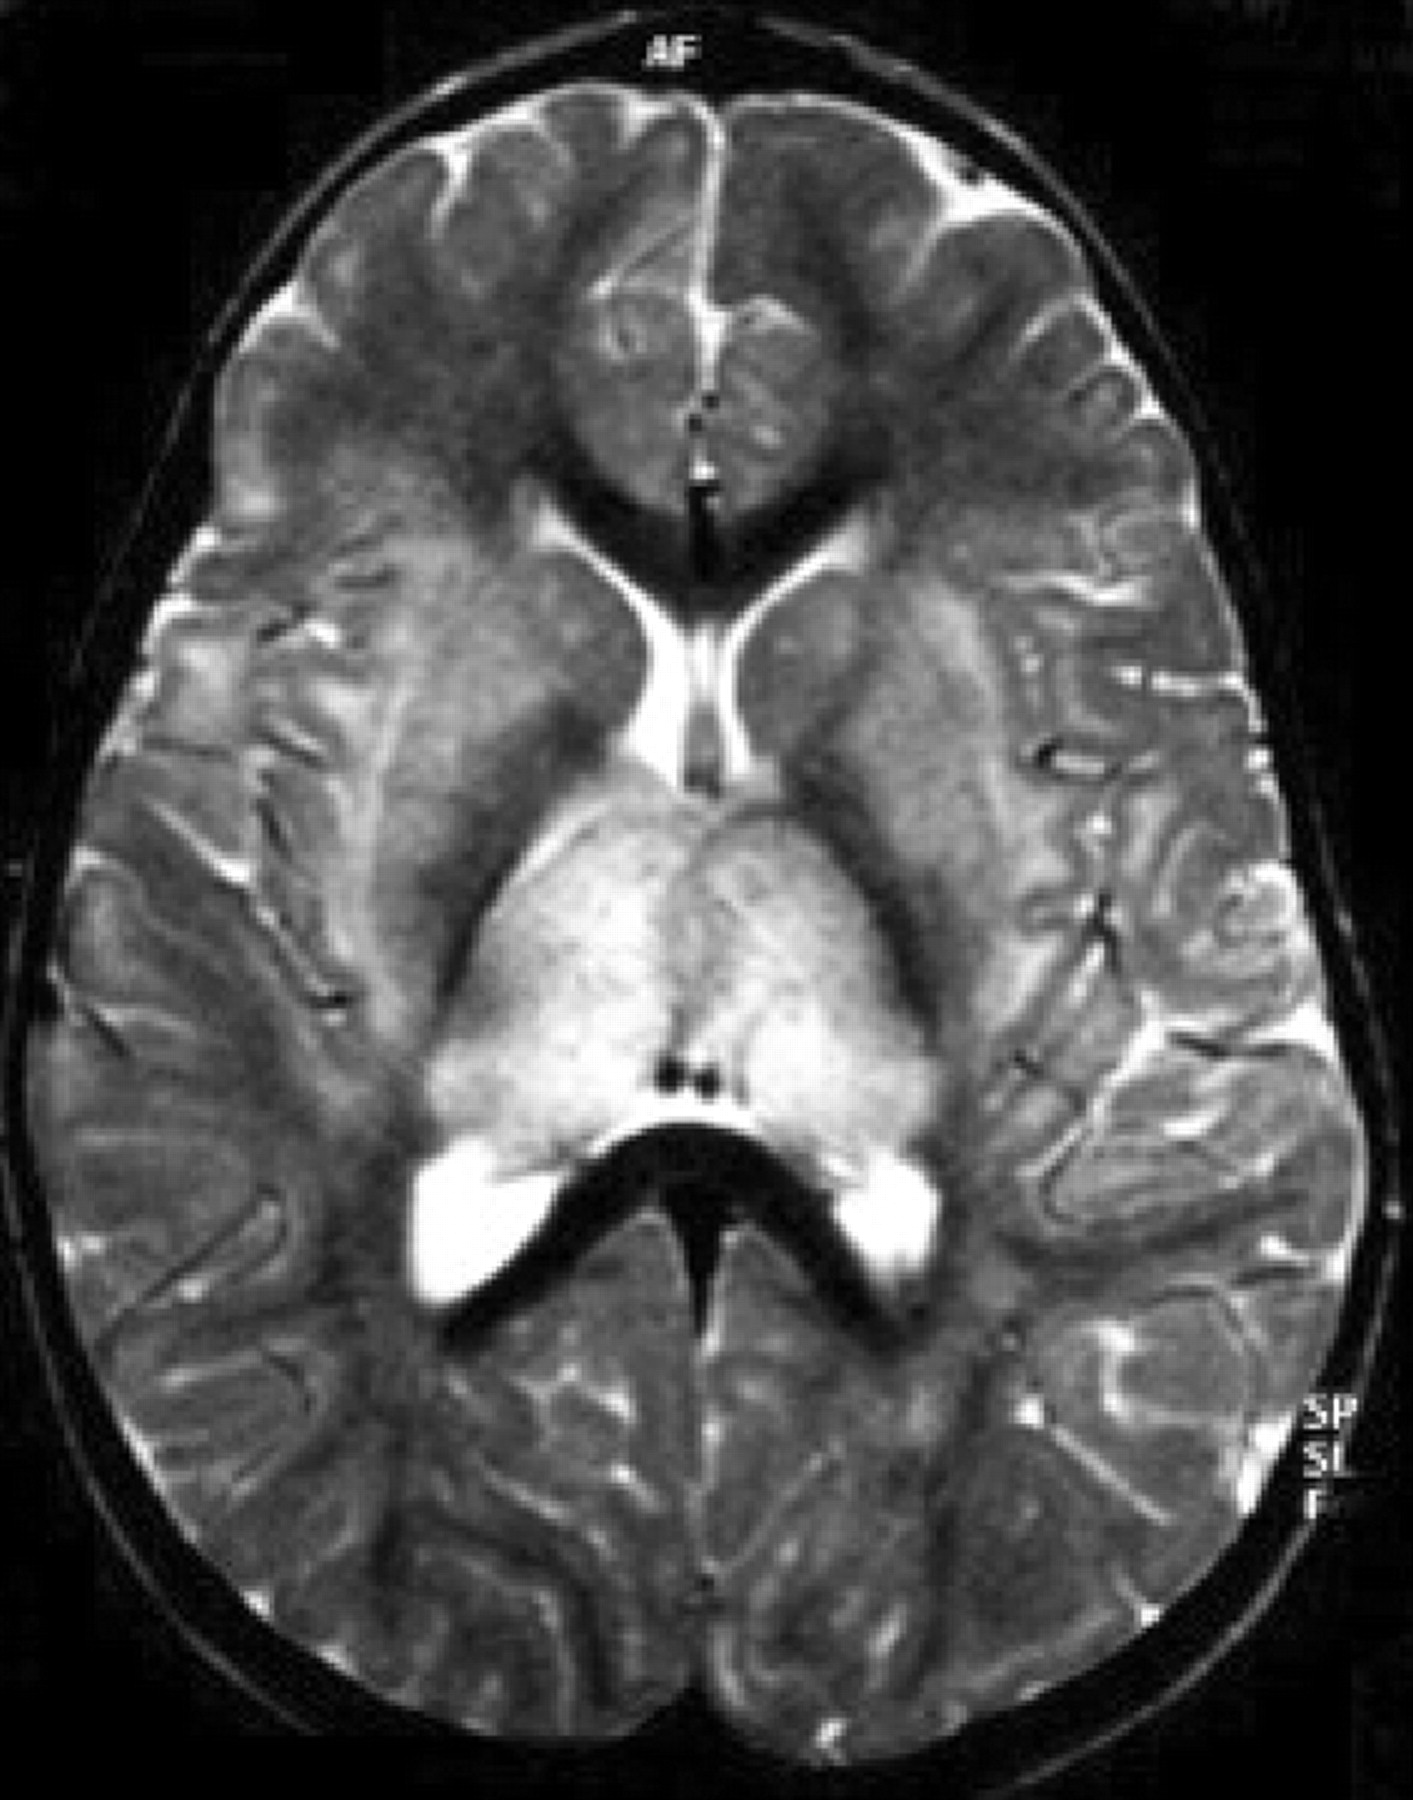

图4。急性出血性脑脊髓炎。(A)轴向t2加权MRI与著名的双边hyperintense病变区域的信号很低,相应的血红蛋白的分解产物,在一个5个月大的孩子男孩,百日咳疫苗接种后2周。(B)轴向t1加权磁共振成像相同的情况下,显示自发hyperintense大hypointense内病变的信号。